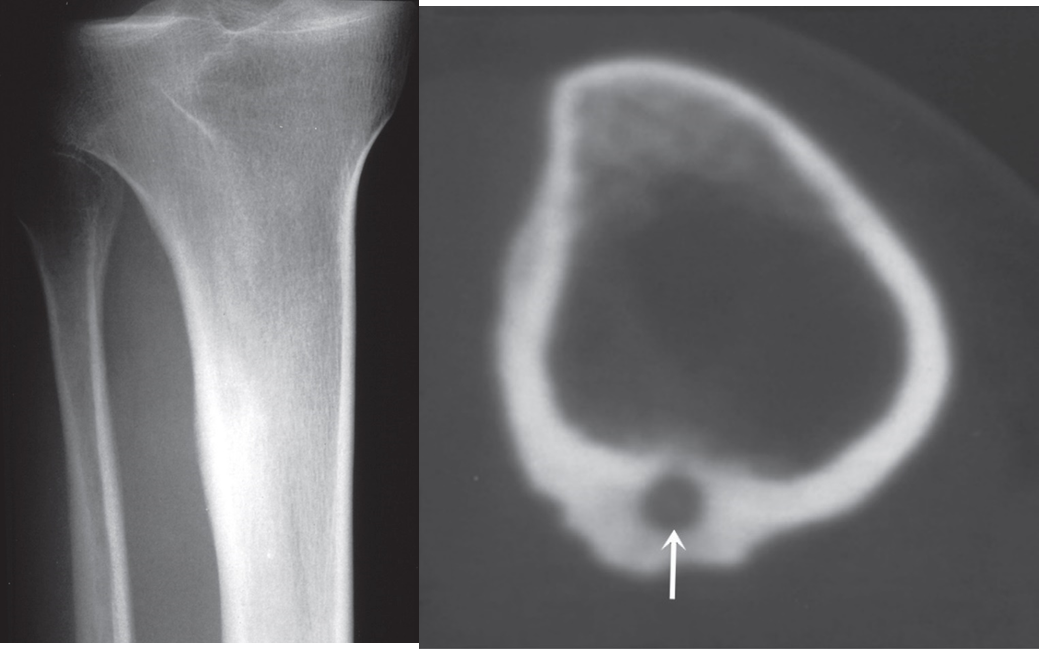

An osteoid osteoma is most common in the femur and tibia in young adults.

characteristic radiological appearance:

- a small lucency, sometimes with central specks of calcification, known as a ‘nidus’, surrounded by a dense sclerotic rim. and classically cause night-pain that is relieved by Aspirin.

(a) Plain film showing an area of sclerosis at the upper end of the tibia.

(b) CT scan showing sclerosis with a central lucency known as a nidus (arrow).